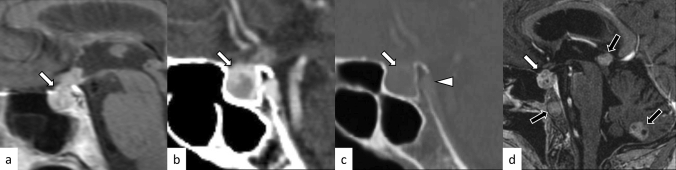

Fig. 1.

A 38-year-old woman with lymphocytic hypophysitis. An enlarged pituitary gland shows heterogeneous hyperintensity on T2-weighted sagittal image (a, white arrow), isointensity on T1-weighted sagittal image (b, white arrow), and homogeneous contrast enhancement (c, white arrow). A dark signal intensity area is observed on the sellar floor (“parasellar T2 dark sign”; a, black arrow). The posterior pituitary T1-weighted bright spot is absent (b, arrowhead). The different images of this case were evaluated in the previous study [9]

Fig. 2.

A 37-year-old woman with lymphocytic hypophysitis. A “snowman-like” shaped enlarged pituitary gland is observed (a–c, arrows). The pituitary gland shows homogeneous hyperintensity on fluid-attenuated inversion recovery (FLAIR) coronal and sagittal images (a, b) and homogeneous isointensity on T1-weighted sagittal image (c). The posterior pituitary T1-weighted bright spot is preserved in this case

Fig. 3.

A 29-year-old man with primary granulomatous hypophysitis. Artifacts due to the patient’s body motion are observed. An enlarged pituitary gland shows heterogeneous hyperintensity on T2-weighted coronal image (a, white arrow), isointensity on T1-weighted coronal image (b, white arrow), and homogeneous contrast enhancement on post-contrast T1-weighted coronal and sagittal images (c, d, white arrows). Extension into bilateral cavernous sinus is observed (e, arrowheads). T2-weighted hypointensity areas around the enlarged pituitary gland are found, suggestive of granulomatous/fibrous inflammation (a, black arrow)